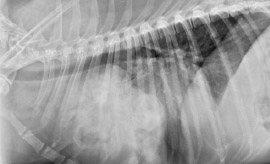

La Importancia de realizar siempre las 3 Proyecciones Radiográficas.

Localización Radiográfica del Lóbulo Pulmonar Afectado para correlacionar el Tipo de Neoplasia.

Caso Clínico

Tanos, macho Boyero de Berna de 10 años se presenta con:

• Dificultad Respiratoria

• Tos Intermitente desde hace 1 mes

• Pérdida de Peso